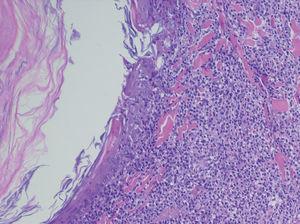

Realizamos una biopsia de una de las lesiones foliculares del abdomen (fig. 3), en cuyo estudio histopatológico apreciamos un infiltrado en banda epidérmico y un denso infiltrado dispuesto alrededor del infundíbulo piloso con afectación de la interfase en dermis. Con técnicas de inmunohistoquímica observamos que dicho infiltrado está compuesto por células linfoides de pequeño a mediano tamaño que exhiben núcleos irregulares e hipercromáticos y expresan el marcador CD3 (fig. 4).

Fig. 3.--Biopsia. (Hematoxilina-eosina, x4.)